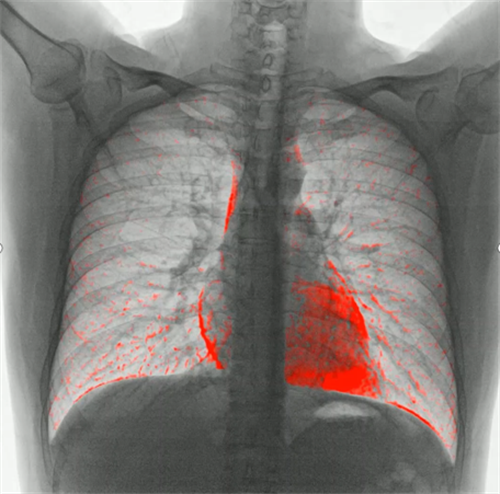

③功能化。当然随着未来对疾病的诊断以及预后评估,功能化发展必然是DR的发展趋势。在肺功能上的应用,可以通过测量呼吸流速、流量分析、肺部通气功能分析等,直观的展现出患者呼吸过程中的通气异常区域,对通气异常及COPD患者提供影像学诊断全新的技术手段。对肺部进行血流灌注分析,来实现在无造影剂条件下对肺栓塞进行评估。还可以应用于骨骼运动方向研究,例如颈椎运动功能成像,骨折修复后愈合状态的评估等。(左边第一张图为肺部血流灌注成像,右边两张图为颈椎运动功能成像)